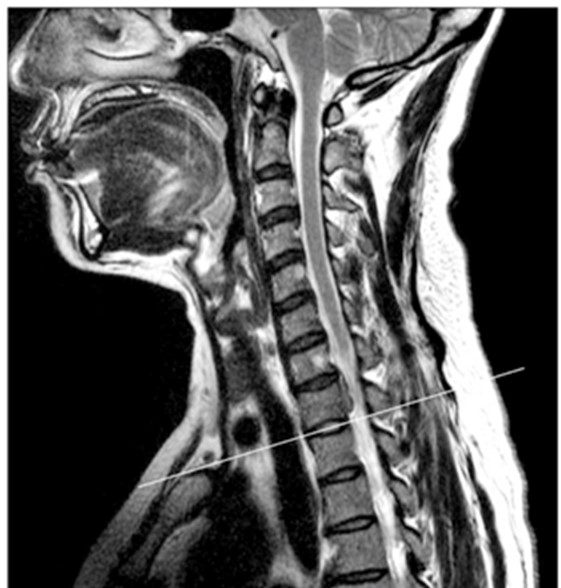

His Neck Disability Index (NDI) scored a 52%. The following is an MRI of his cervical spine taken after this work related injury.

52 yo neck pain